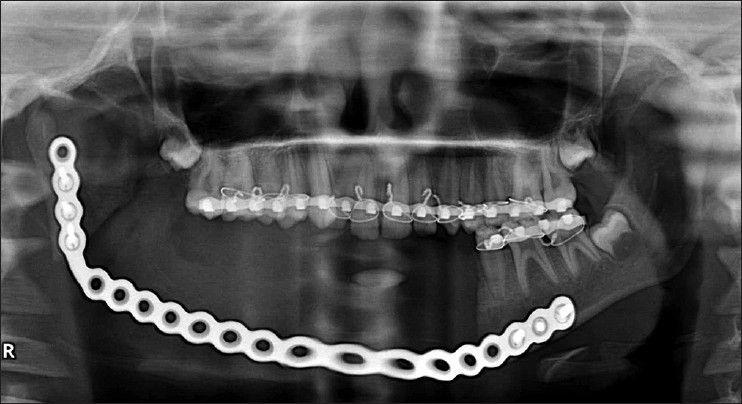

Ossifying fibromas are well-demarcated benign fibro-osseous tumors of craniofacial skeleton most often in the jaws. It has two types, conventional and juvenile ossifying fibroma (JOF). JOF is considered a separate entity from ossifying fibroma due to its locally aggressive behavior and tendency to occur at a young age. Two subtypes of JOF, i.e., juvenile psammomatoid ossifying fibroma (JPOF) and juvenile trabecular ossifying fibroma have been identified on the basis of histology 70% of the JPOF occur in the paranasal sinuses, 20% in the maxilla and only 10% in the mandible. Here, we report a case of JPOF in a 14-year-old girl causing an asymptomatic expansile swelling in the right mandibular posterior region, which is a rare site for this tumor.

骨化性纤维瘤是颅面骨骼中界限清楚的良性纤维骨性肿瘤,最常发生于颌骨。它有两种类型,即传统型和青少年骨化性纤维瘤(JOF)。由于其局部侵袭性和发病年龄较轻的倾向,JOF被认为是与骨化性纤维瘤不同的实体。根据组织学特征,JOF已被鉴定出两种亚型,即青少年砂粒样骨化性纤维瘤(JPOF)和青少年小梁状骨化性纤维瘤。70%的JPOF发生于鼻窦,20%发生于上颌骨,仅10%发生于下颌骨。在此,我们报告一例14岁女孩的JPOF病例,该肿瘤导致右下颌后区出现无症状性膨胀性肿块,而这一部位发生该肿瘤较为罕见。